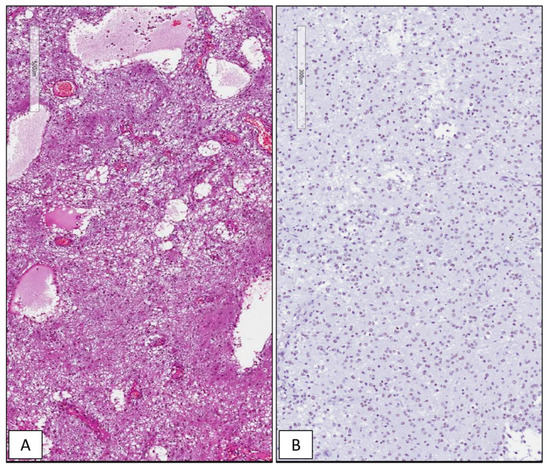

3.2. Differential Immunohistochemical Expression of SRSF1 in Adult Gliomas